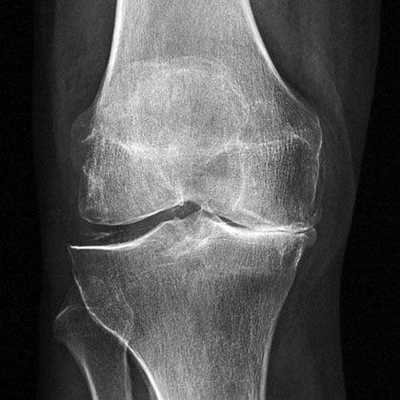

Артроз коленного сустава на рентгене.

Посмотрите на рентген, на нем вы видите, до какой степени при запущенном гонартрозе изношен гиалиновый хрящ, обеспечивающий гладкое скольжение суставных поверхностей. Концевые участки костей грубо деформируются нарушая функции сгибания и разгибания конечности вызывая интенсивный болевой синдром.

Сравнение здорового и пораженного сустава.